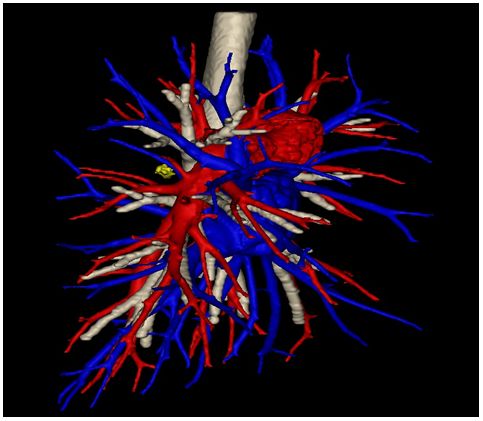

原标题:【医疗】三维重建助力胸外科完成多例精准肺段切除术 患者术前胸部CT检查结果,箭头所指处为病灶,表现为磨玻璃样结节 45岁患者王女士家住丹东市,体检时发现右肺下叶磨玻璃密度小结节,影像学上符合早期肺癌的表现,王女士及家人非常焦虑,四处求医。医生给王女士的建议都是手术切除。王女士肺部的病灶虽然体积较小,直径约1cm,但由于病变靠近肺门深处,采用常规的肺楔形切除手术非常困难,甚至可能对肺组织造成较大的损伤。如果行肺叶切除,王女士又担心术后肺功能的损失较多,恐怕术后不能从事繁重工作。王女士接受手术治疗的意见,但是她希望手术的效果是即能切除病灶,又可以最大限度的保留正常肺组织。经地方医院介绍,王女士来到我院第二胸外科病房找到了石文君主任。 入院后,王女士进行了胸部增强CT+三维重建的检查,随后进行了支气管血管三维重建,根据三维重建的结果,石主任带领团队为王女士制定了精准肺段切除的手术方案。由于术前已经从三维重建图像中得知了血管及支气管的变异,手术进行的非常顺利,手术时间及出血量均较常规的肺叶切除手术无明显差别,术后王女士恢复顺利并出院。现王女士术后已有半年,来复查时欣喜地告诉我们,目前她仍可以从事之前较为繁重的工作,体力上也相当充沛。目前类似于王女士这种情况的患者非常多,第二胸外科病房现已完成多例胸腔镜下精准肺段切除术,帮助患者获益。 三维重建立体图像,白色为支气管,红色为动脉,蓝色为静脉,黄色为病灶所在位置 支气管及肺动静脉3D打印模型 胸腔镜肺段切除术是早期肺癌的重要治疗手段之一,精准的手术是肿瘤学疗效和肺功能保护的前提。精准肺段切除术的目标是在彻底切除病灶的同时最大程度地保留健康肺组织。但是精准肺段切除最大的难点在于每个人解剖的不确定性,因为肺血管、支气管细枝末节就像一棵树,每个人长得都不一样。要做到精准切除,首先就要确定病变在哪一个肺段,其次需要精确判断该肺段的动脉、静脉、支气管有没有畸形,需要切断哪一个,保留哪一支。这些信息都需要三维重建图像提供给我们,所以说“无重建,不精准”。 目前高龄患者及肺小结节的患者很多,精准肺段切除非常适合这类肺小结节或无法耐受肺叶切除的高龄患者的治疗。开展精准肺段切除的最大难点准确分辨肺段的静脉、动脉、支气管及段间平面,有3D-CTBA重建影像指导的肺段切除术才是精准肺段切除术。我院第二胸外科病房将三维重建及3D打印技术应用到肺段切除术前,做到“精准”肺段切除。术前对拟行肺段、肺亚段切除病例行薄层CTA检查,获得DICOM影像资料在计算机上使用软件进行三维重建,生成立体图像在三维图像上进行测量,提前发现患者存在的解剖变异,规划手术区域及手术径路,设计手术方案,选定需要切断的靶血管及支气管和需要保留的血管及支气管,设计段间切割线胸腔镜手术,根据术前的规划完成手术。因术前进行了准确的三维重建,可以在手术开始前及时发现解剖变异,在术中准确辨认所需切除术的血管及支气管,防止误断,提高了手术的精确性及安全性避免了因复杂的肺段解剖而带来的问题。 在日前由我院第二胸外科病房举办的“2019盛京医院胸外论坛暨盛京第一届精准肺段研讨沙龙”上,石文君主任主持大会。北京大学人民医院李剑锋教授等多名国内胸外科专家应邀参会并作了“近红外荧光显像在肺段切除中的应用探索”等专题报告,还进行了单操作孔胸腔镜下左肺下叶前基底段切除的手术演示。 在石文君主任的带领下,第二胸外科病房除了常规开展胸腔镜肺癌根治术、食管癌根治术、纵隔肿瘤切除术外,目前已成熟掌握并开展精准肺段切除术。但是对于临床分期不同的肺癌,其治疗效果差异较大,只有早期肺癌才有接受“精准肺段切除”治疗的机会,其手术创伤小,能彻底切除目标病灶,最大限度减免肺组织损伤,确保剩余肺结构完整和功能代偿。因此在肺癌的治疗中,早期发现尤为重要,建议特别是45岁以上、有吸烟史、家族遗传倾向的高危人群,应每年进行一次胸部CT检查;对于上述高危因素的人群,也应适时进行体检,争取做到早期发现及治疗。